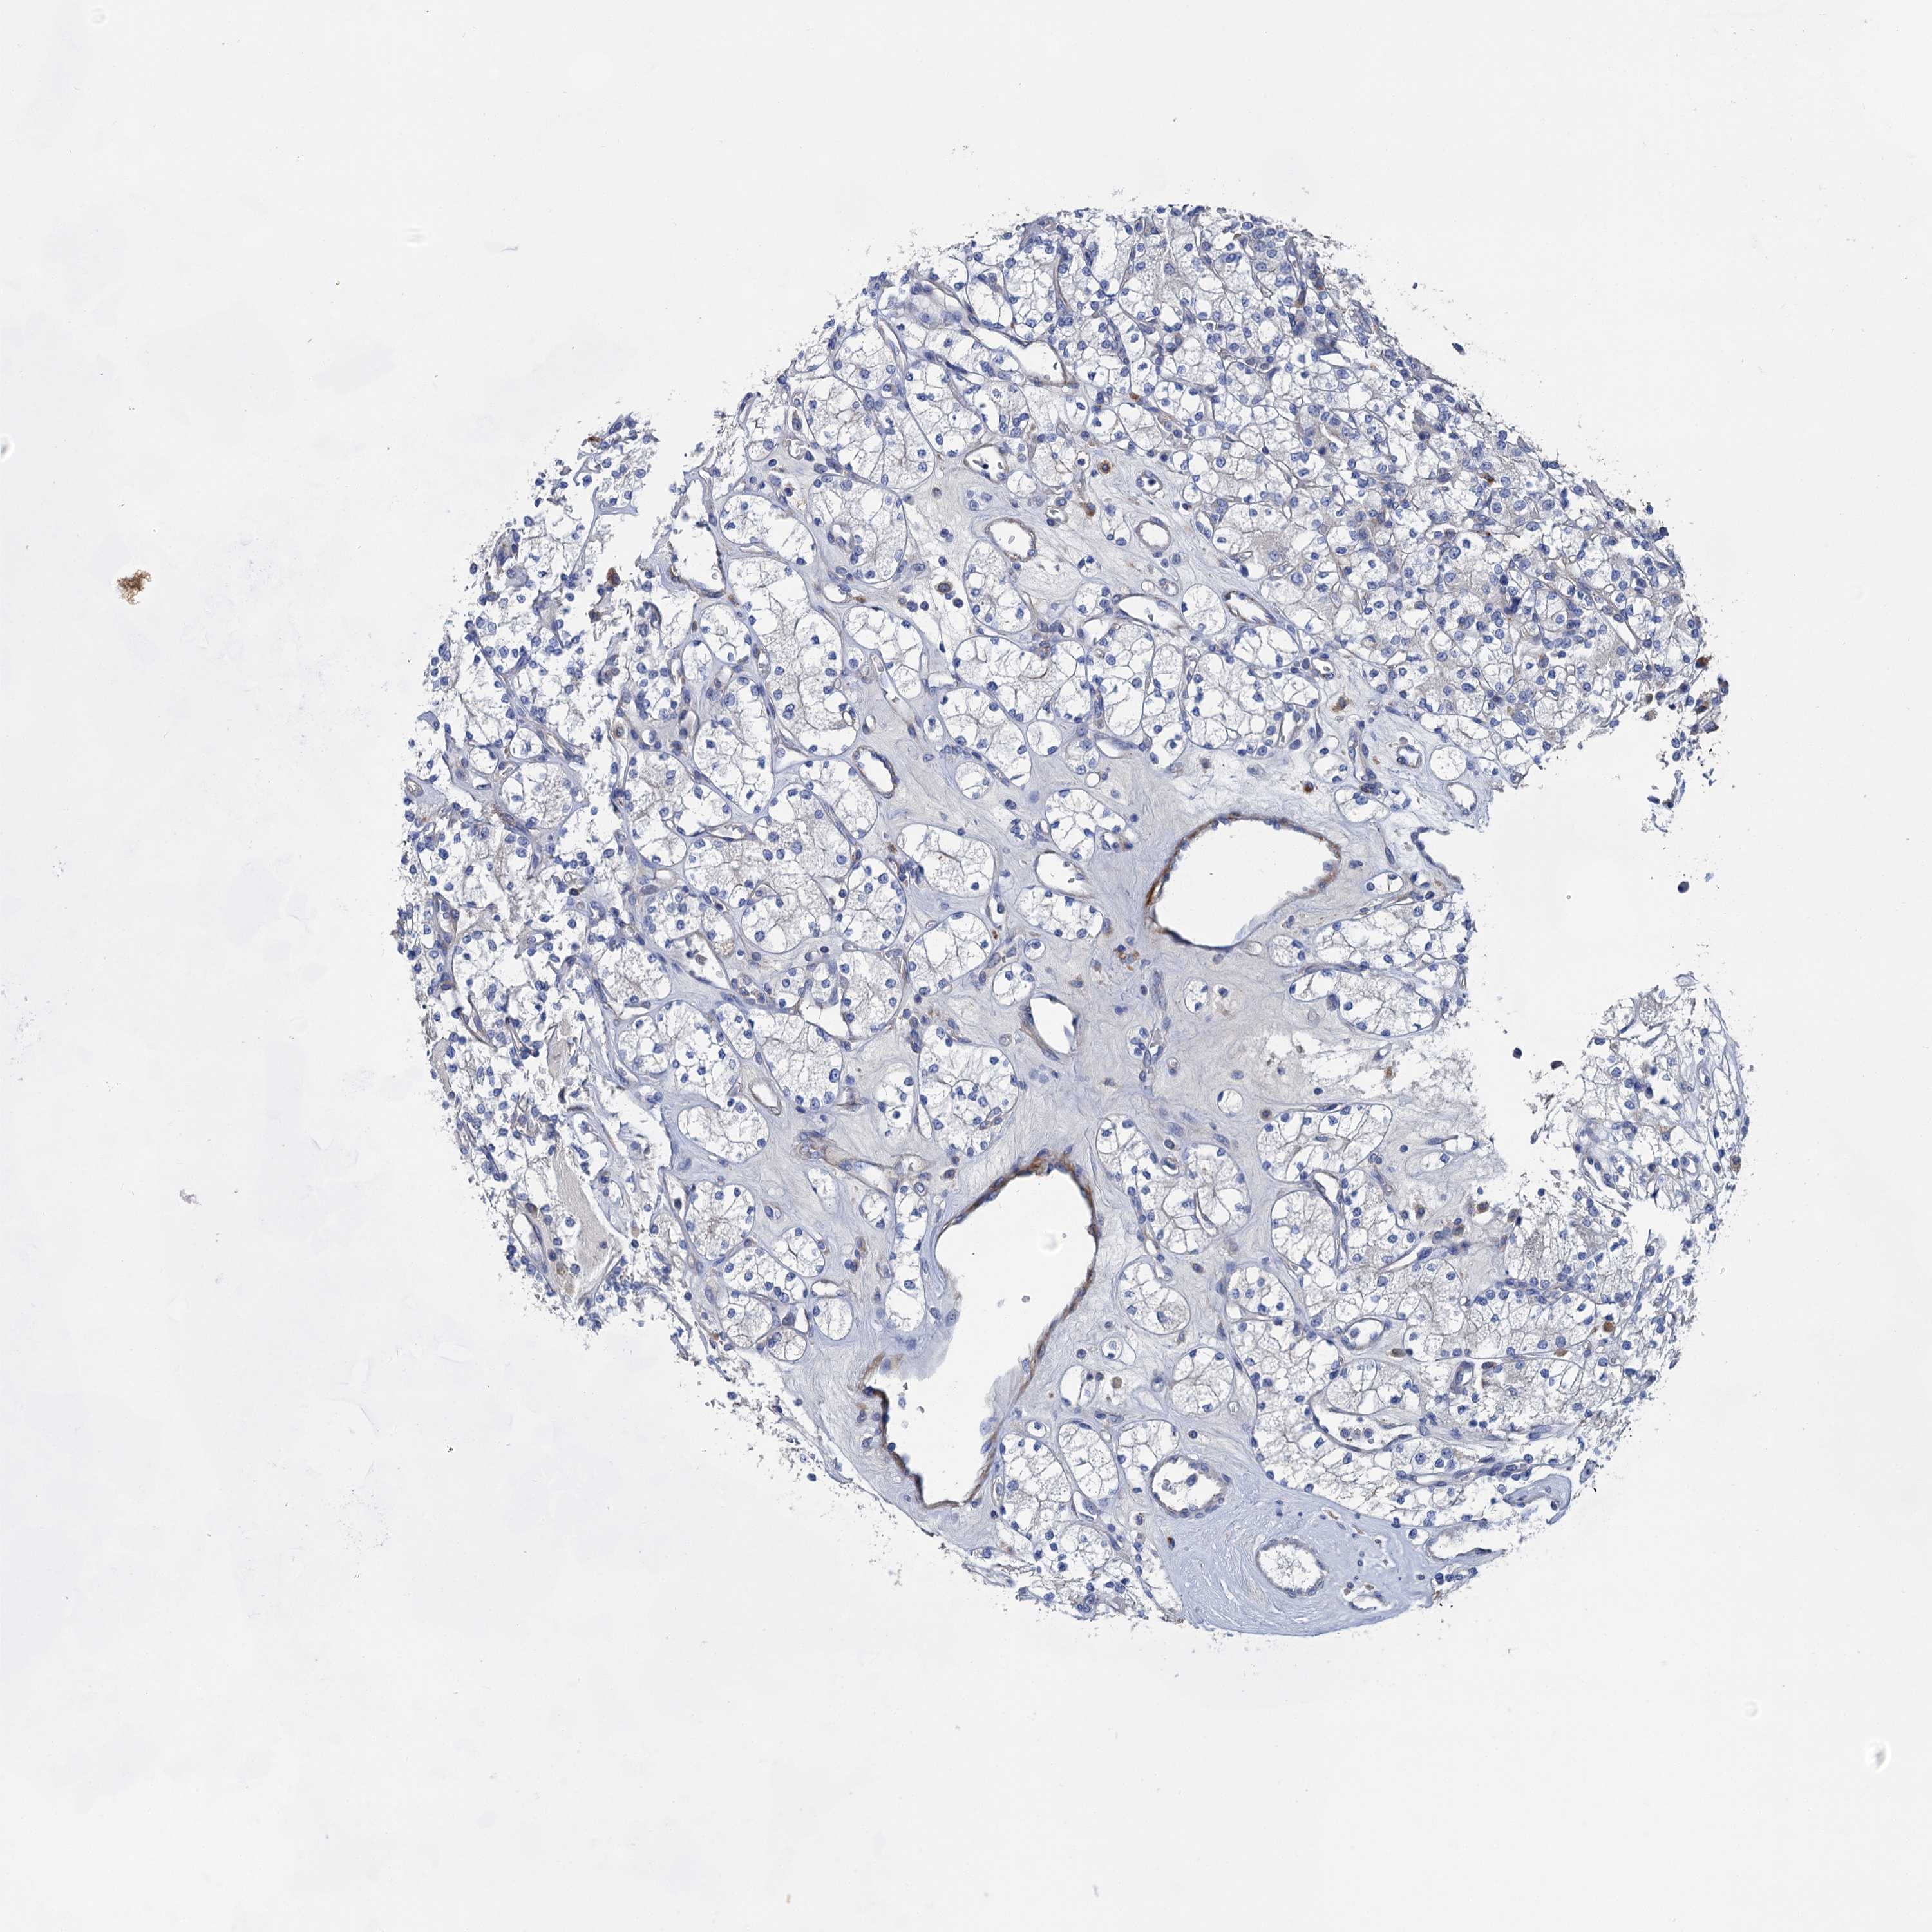

CANCER RENAL CANCER Show tissue menu

KICH TCGA KIRC TCGA KIRC VALIDATION KIRP TCGA PROTEIN RCC CPTAC PROTEIN EXPRESSION